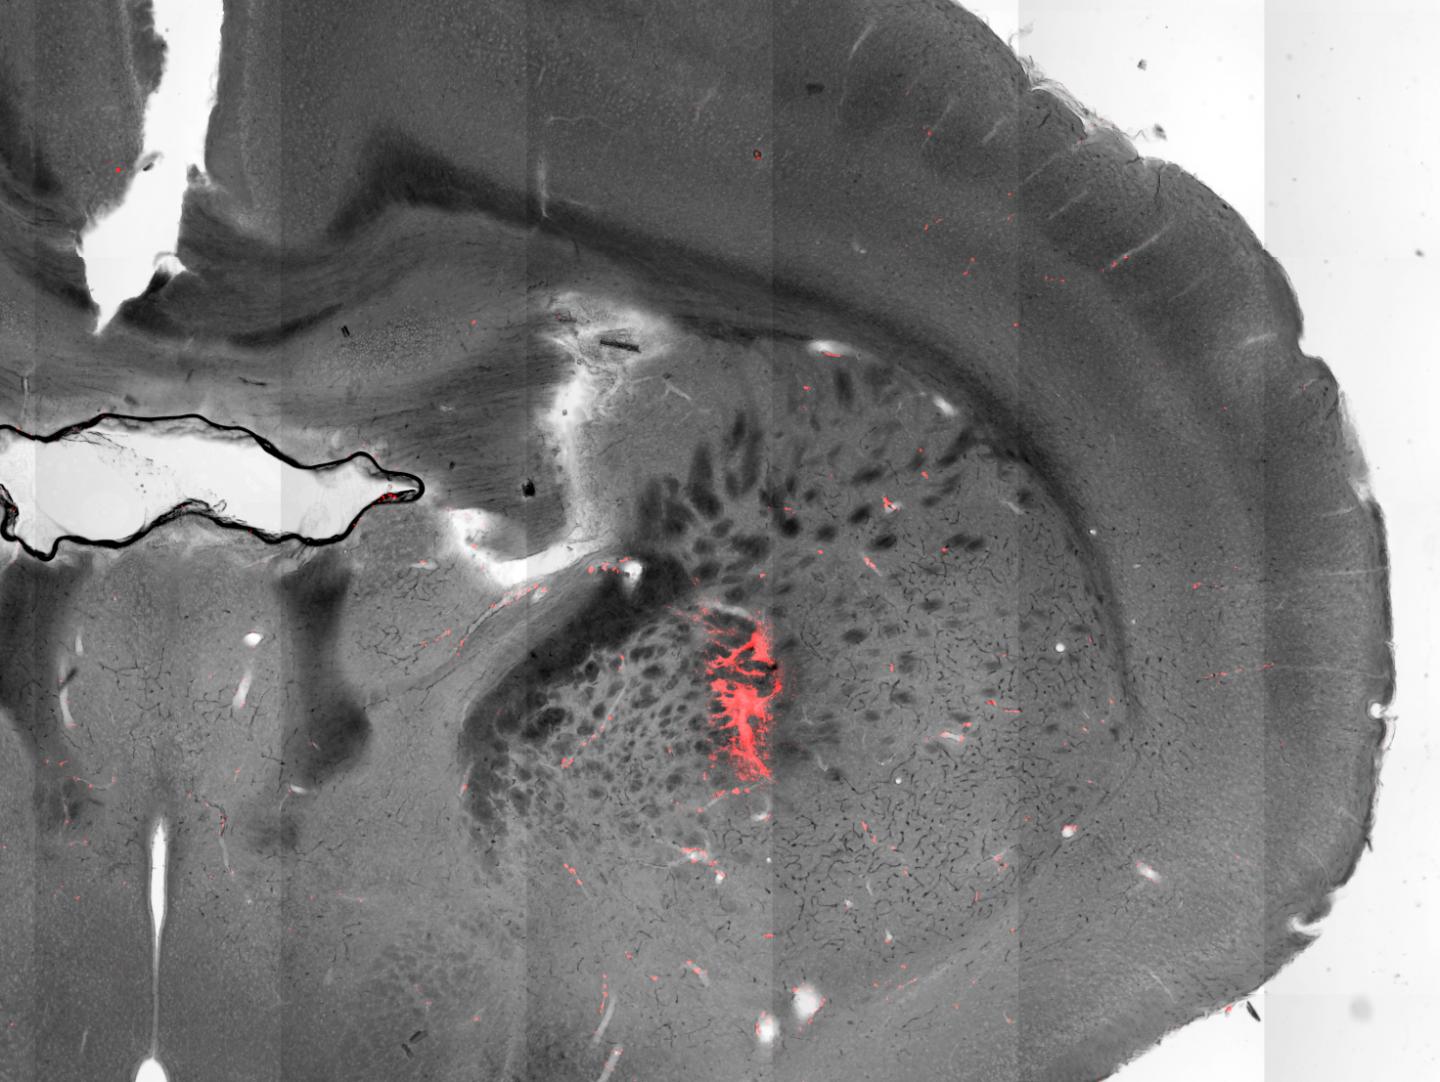

In mice, Pralle's team succeeded in activating three distinct regions of the brain to induce specific motor functions.

Stimulating cells in the motor cortex caused the animals to run, while stimulating cells in the striatum caused the animals to turn around. When the scientists activated a deeper region of the brain, the mice froze, unable to move their extremities.

"Using our method, we can target a very small group of cells, an area about 100 micrometers across, which is about the width of a human hair," Pralle says.

Here's how it works: First, scientists use genetic engineering to introduce a special strand of DNA into targeted neurons, causing these cells to produce a heat-activated ion channel. Then, researchers inject specially crafted magnetic nanoparticles into the same area of the brain. These nanoparticles latch onto the surface of the targeted neurons, forming a thin covering like the skin of an onion.

When an alternating magnetic field is applied to the brain, it causes the nanoparticles' magnetization to flip rapidly, generating heat that warms the targeted cells. This forces the temperature-sensitive ion channels to open, spurring the neurons to fire.

The particles the researchers used in the new eLife study consisted of a cobalt-ferrite core surrounded by a manganese-ferrite shell.